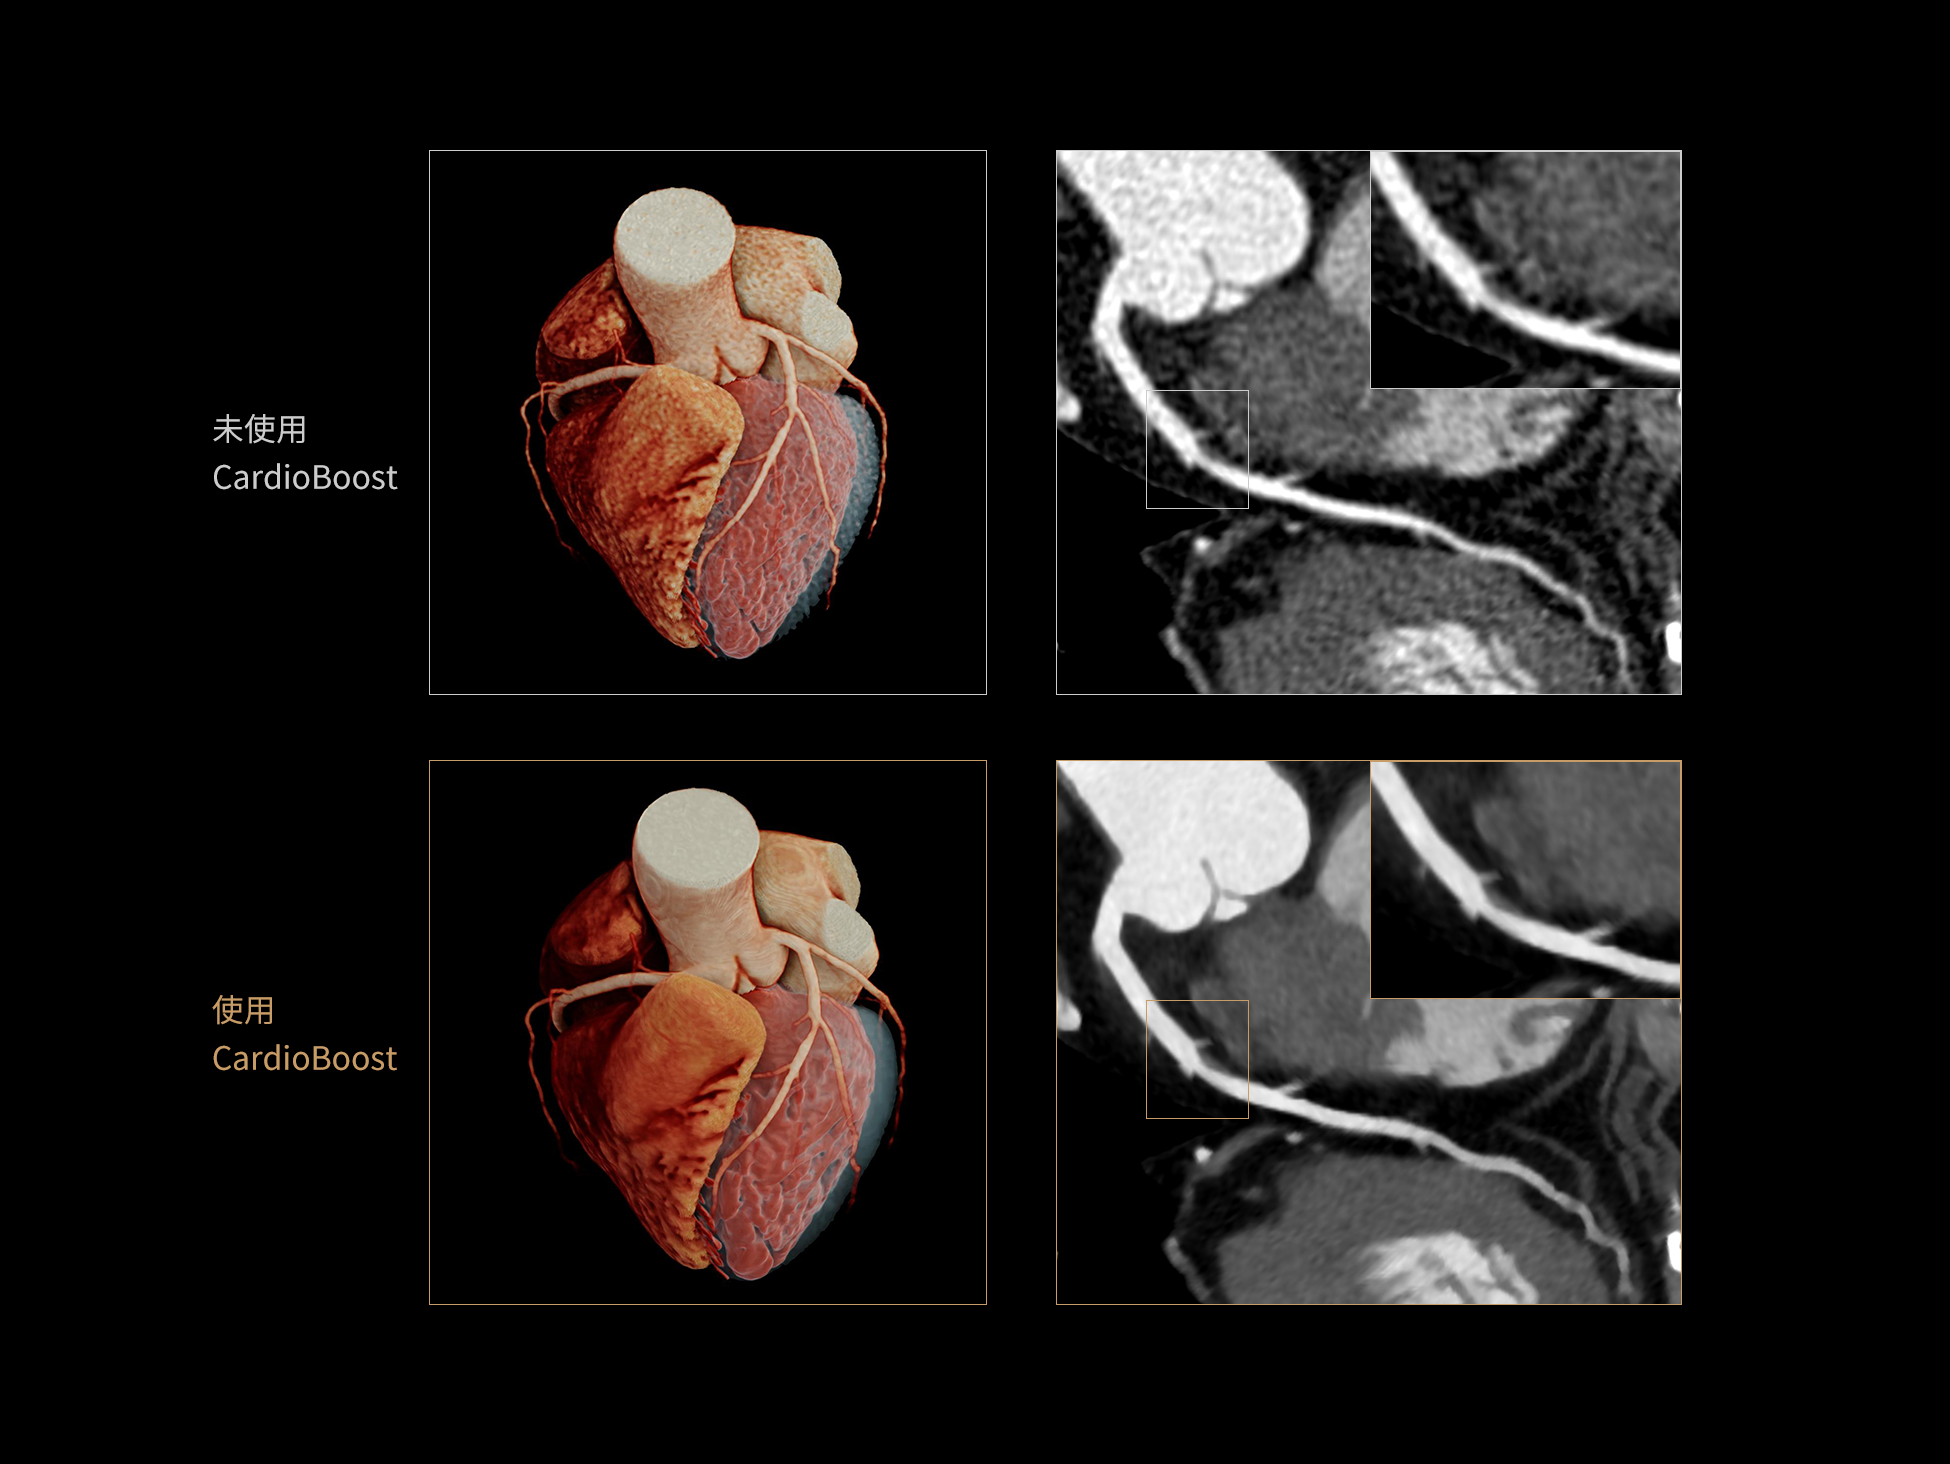

CardioBoost:专属网络设计,重塑心脏影像表现

uCT 868 搭载联影最新一代 uSense 人工智能平台,将智能化深度融入 CT 扫描全流程,从感知细微生理运动到精细结构探测,再到多场景诊疗优化。以 AI 为核心驱动力,uSense 重塑成像各环节,打造高效、高清的智慧扫查体验。在心脏成像领域,uSense 结合宽体探测器、心脏专研AI重建算法与AI冠脉运动追焦技术,在保持低剂量的同时,有效抑制运动伪影,精准呈现软斑块、混合型斑块及支架细节,助力冠脉成像惠及更多患者。针对多科室疾病临床应用场景,uSense 平台提供全方位的智能解决方案:包括头部运动伪影智能校正、金属植入物伪影抑制、扫描视野扩展等先进算法。这些创新技术使 uCT 868 能够构建覆盖全场景的智能诊疗体系,持续拓展 AI 赋能医学影像的边界。